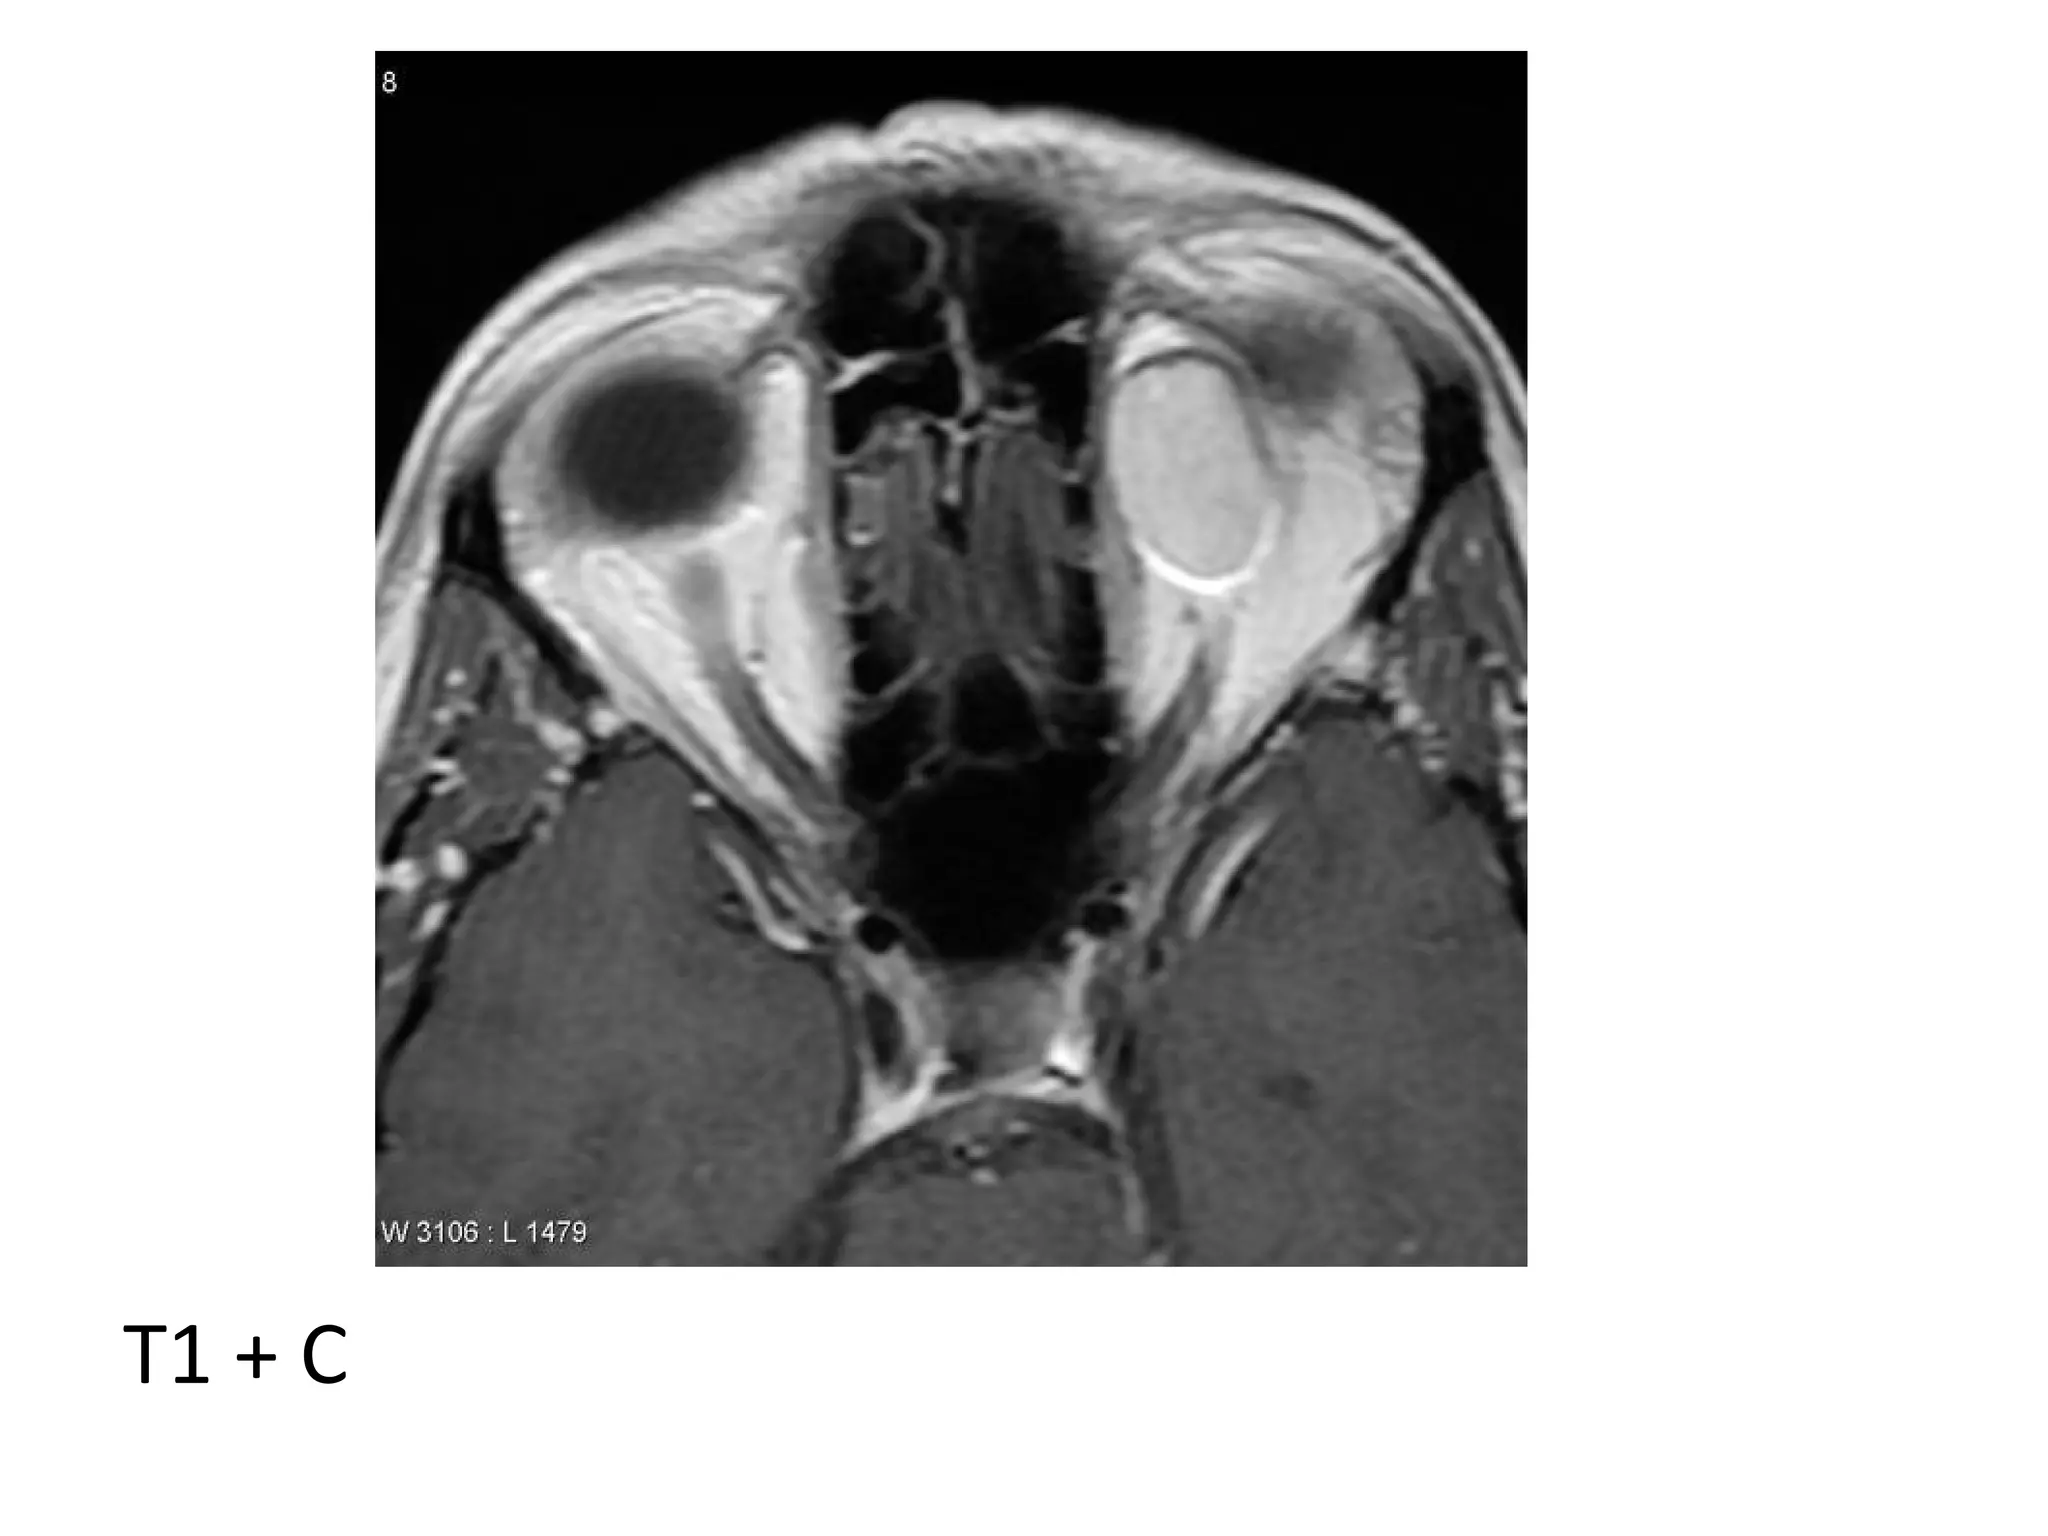

2-MRI :

*T1+C : The tumor enhances

T1

T2

T1+C